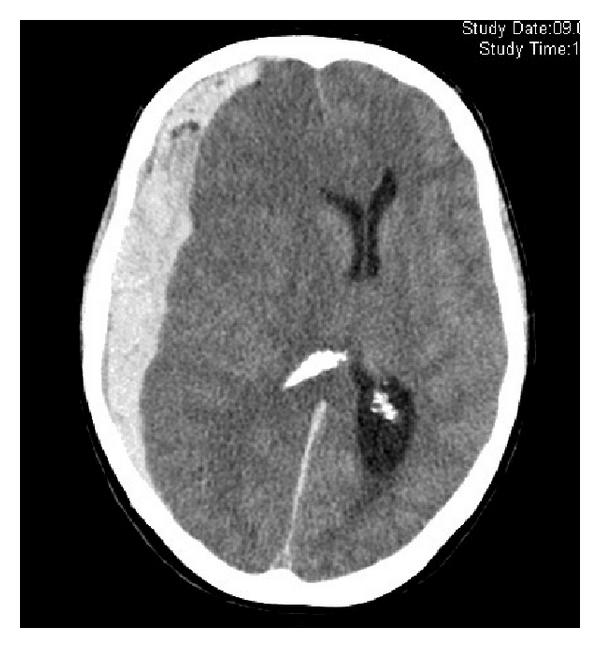

出血性中風

原因多為高血壓或腦血管病變,令血管破裂,血液流出,令腦神經受損。症狀一般來得急而且嚴重,如血液擠壓腦部令壓力升高,可致嚴重頭痛、嘔吐、神志不清,甚至昏迷。必須立即送院,找出出血位置而決定治療方案。